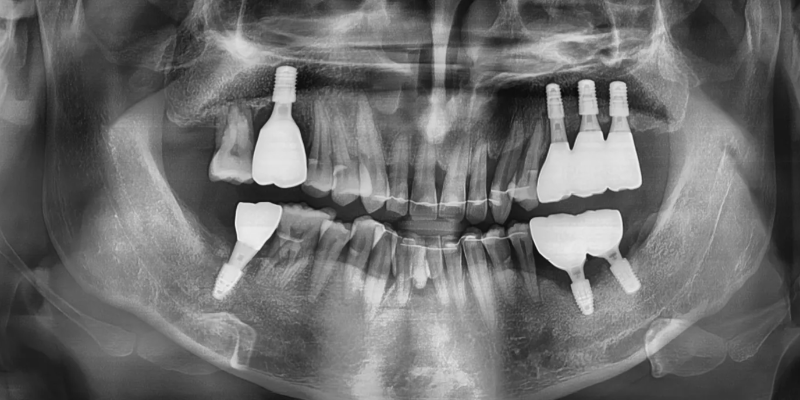

우측 위아래는 최종보철을 완성하여

식사를 조금이라도 하실 수 있도록 진행하였으며

왼쪽 아래는 첫번째 큰 어금니 식립과 함께

보철을 연결하기위해서

현재 식립한 임플란트에는 임시치아를 제작하여

다음 과정 전까지 사용하기로 하였습니다.

앞니 교정을 마무리하면서

기존에 발치를 했던 아래의 앞니부분은

브릿지로 빠르게 수복 완료한 뒤

유지장치를 부착하였습니다.

동시에 왼쪽위의 어금니는 발치 후

치조골이식술을 동반하여

임플란트를 3개 식립하였습니다.

치조골과 임플란트가 골유착되는

치유의 시간을 충분히 기다린 뒤

왼쪽 위 보철도 마무리하였습니다.

마지막으로 왼쪽 아래의 첫 번째 큰어금니도 발치한 뒤

임플란트 식립을 진행하였습니다.

이후 왼쪽 맨 뒤의 임플란트에

장착했던 임시치아는 제거하고

왼쪽의 큰 어금니 부위에 스플린트 브릿지로

최종 보철을 완성하였습니다.